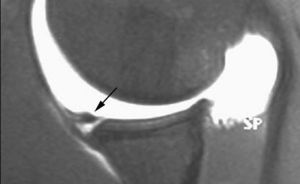

Lesión de Perthes

La lesión de Perthes es similar a la de Bankart, con la excepción de que no existe rotura capsuloperióstica, aunque el periostio puede estar separado del borde anterior del margen glenoideo (fig. 10). Esta lesión puede ser difícil de visualizar, incluso con artrorresonancia, a menos que se obtengan imágenes con la posición de abducción y rotación externa (ABER). En un estudio de 10 casos, verificados quirúrgicamente, Wisher et al17 comprobaron que el 50% de las lesiones de Perthes sólo podían visualizarse en la posición de ABER.

Fig. 10.--Lesión de Perthes. Artrorresonancia T1 con saturación grasa en posición ABER (abducción y rotación externa), donde se observa un arrancamiento parcial del labio glenoideo (flecha) con conservación de la unión capsuloperióstica.